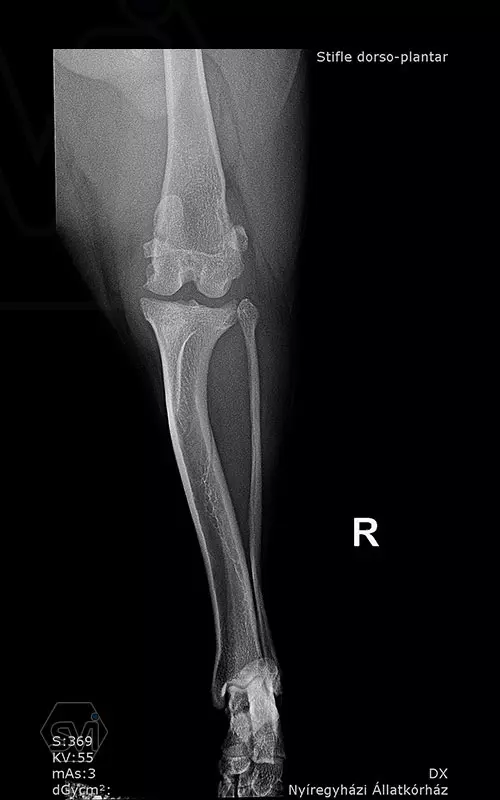

1,5 year old 13 kg mix dog underwent surgery today due to cranial cruciate ligament rupture and concomitant grade 3/4 medial patella luxation. During surgery, lateral tightening and medial loosening of the joint capsule (without opening the capsule) was performed. In the first phase of surgery, the 26-degree TPA was corrected simultaneously with the medial transposition of the proximal fragment. An R18 TPLO blade was used and the step and the rotation was fixed with a 2.7 precontured TPLO plate. The big curvature of the precontured plate provided an opportunity for placement without further conuring of the plate. The plate was temporarily fixed to the bone surface with two 1.2 K-nails using holes for temporary fixation. The distal piece was first stabilized with two locking screws. An AO 2,7mm srew was placed in the cranial hole of the proximal piece, which was able to create a significant tuberositas tibiae shift by tightening and simultaneously removing the temporaly, rotation stabilizing K-wire. Polyaxial locking screws are inserted into the remaining holes.

Thus, during surgery, we successfully applied a member of the precontured plate family designed for 2.7 mm screws for TPLO-M surgery.